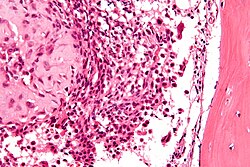

Microscopic

Features:

- Fibrosis.

- +/-Giant cells with round to oval nuclei and nucleoli.[10]

- Bone unaffected by tumour - increased numbers of the following:

- Multinucleated cells (osteoclasts).

- Mononuclear cells around the bony trabeculae (osteoblasts).

DDx:

- Giant cell tumour of bone and other giant cell lesions.

Images

- Brown tumour - low mag.jpg

Brown tumour - low mag. (WC)

- Brown tumour - intermed mag.jpg

Brown tumour - intermed. mag. (WC)

- Brown tumour - high mag.jpg

Brown tumour - high mag. (WC)